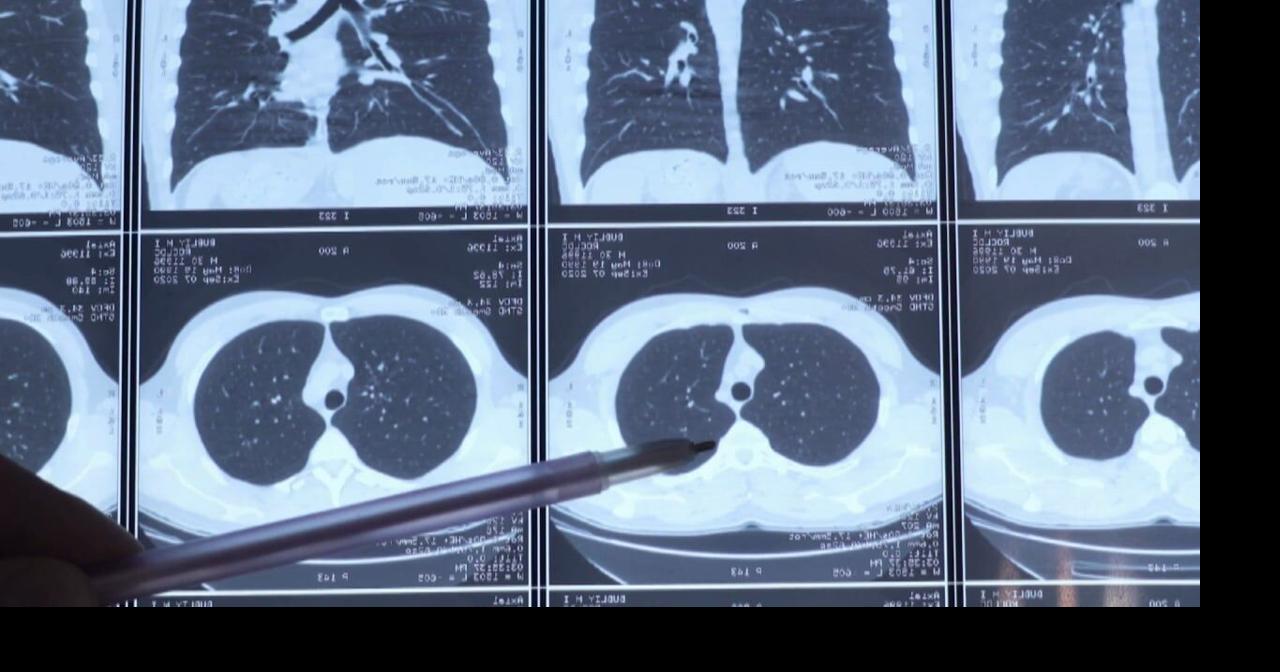

Un nuevo robot en Eureka está revolucionando el diagnóstico temprano y tratamiento del cáncer de pulmón, lo que podría aumentar significativamente las tasas de supervivencia de esta enfermedad mortal.

- El nuevo robot introduce tecnología avanzada que permite procedimientos de tratamiento más precisos y efectivos, facilitando una detección más temprana del cáncer de pulmón.